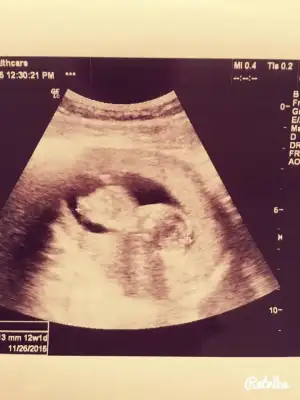

Kızlar anlayan yorum yapabilir mi :) 11+1 usg goruntusu

Kızlar bana da yorum yapabilirmisiniz belli oluyor mu bilmiyorum ama açıkçası ben pek anlamıyor bebisim fotoda 12+4 haftalık tüp bebekle oldu sizce cinsiyeti nedir doktor ancak 16. Haftada söyleyebilirim dedi 12 haziranda bir daha ki kontrolüm çok merak ediyorum lütfen yardımcı olun

Kızlar bana da yorum yapabilirmisiniz belli oluyor mu bilmiyorum ama açıkçası ben pek anlamıyor bebisim fotoda 12+4 haftalık tüp bebekle oldu sizce cinsiyeti nedir doktor ancak 16. Haftada söyleyebilirim dedi 12 haziranda bir daha ki kontrolüm çok merak ediyorum lütfen yardımcı olunEki Görüntüle 1528009